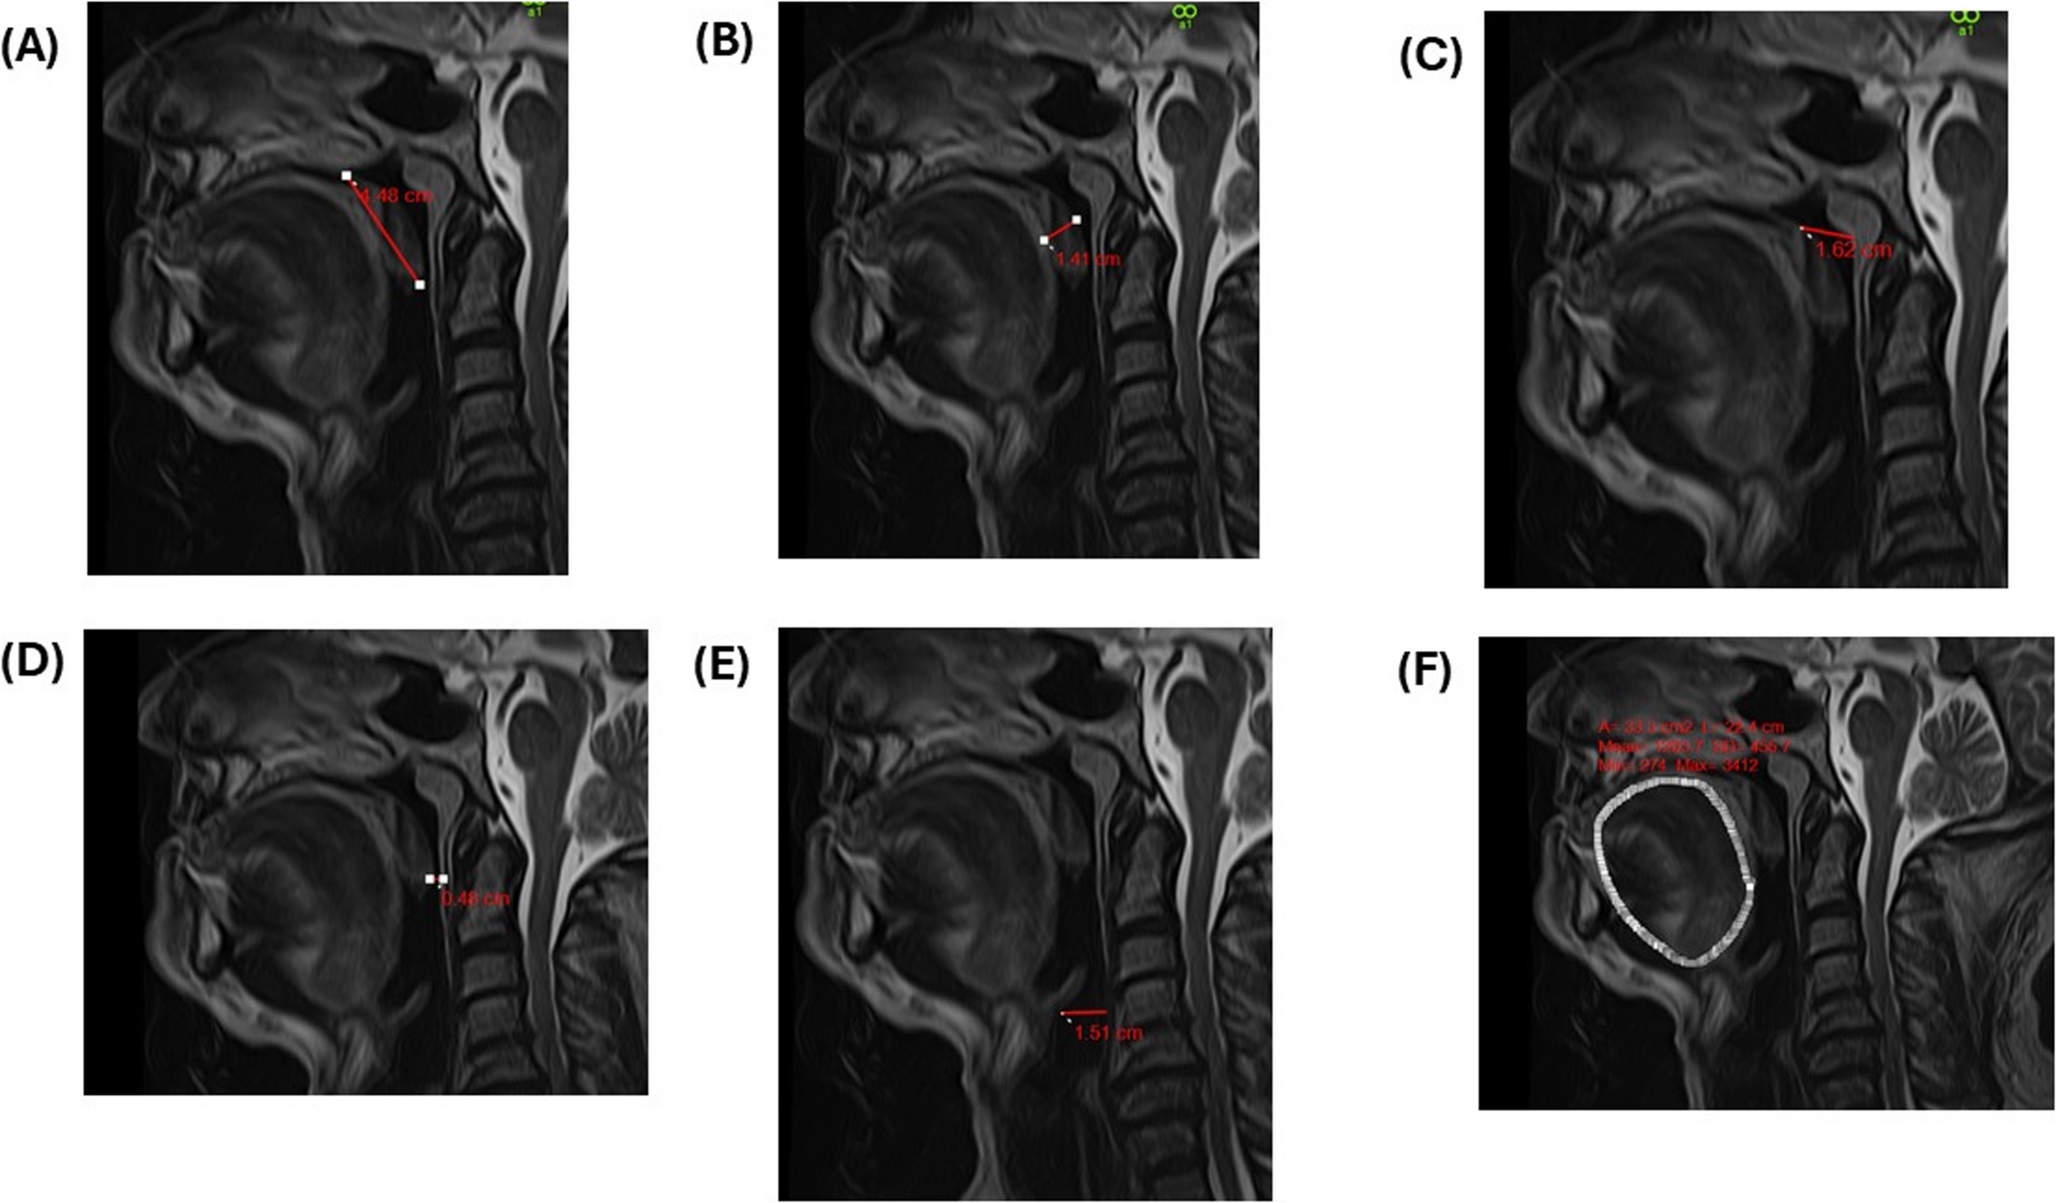

Fig. 4

Postoperative MRI images for assessment of the same patient illustrated in Fig. 3 with a postoperative (A) MLSP of 44.8 mm, (B) MTSP of 14.1 mm, (C) PNAS of 16.2 mm, (D) OPAS of 4.8 mm, (E) MPAS of 15.1 mm, and (F) tongue Volumes with a maximum volume of 74.6mL. MRI – Magnetic Resonance Imaging; MLSP – Maximum Length of the Soft Palate; MTSP – Maximum Thickness of the Soft Palate; PNAS – Posterior Nasal Airway Space; OPAS – Occlusal Posterior Airway Space; MPAS – Mandibular Posterior Airway Space

Post-operative MRI analyses, conducted 12 months after SG, revealed a profound anatomical remodeling associated with improved upper airway patency (Fig. 4). PNAS demonstrated a significant increase to 11.3 ± 0.4 mm (p < 0.001) (Fig. 5). Tongue volume exhibited a marked reduction of 18.5%, decreasing from 102.6 ± 1.9 mL to 83.7 ± 1.5 mL (p < 0.001), indicative of a substantial reduction in soft tissue bulk at the tongue base, thereby mitigating posterior airway collapse. Notably, MLSP and MTSP dimensions demonstrated significant reductions postoperatively, with MLSP decreasing to 36.2 ± 0.3 mm and MTSP to 10.8 ± 0.2 mm (p < 0.001), highlighting the alleviation of soft tissue crowding in the oropharyngeal region (Fig. 5). Concomitant improvements in OPAS and MPAS were observed, with OPAS expanding to 7.4 ± 0.3 mm and MPAS increasing to 11.2 ± 0.4 mm (p < 0.001), reflecting enhanced posterior airway patency and improved airflow dynamics (Table 2) (Fig. 5).